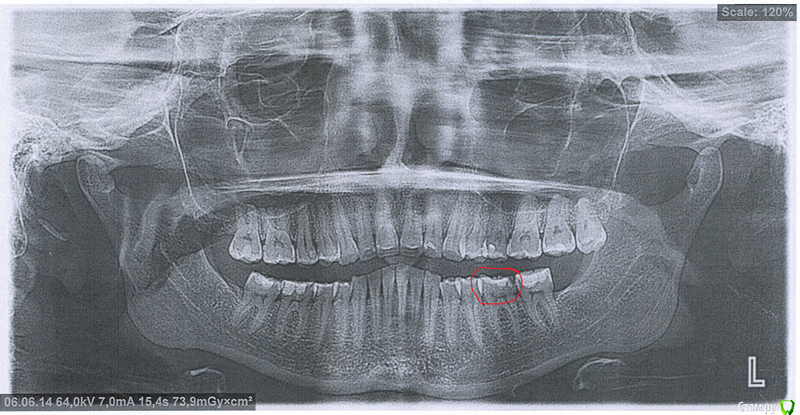

smeshik Опубликовано 27 мая, 2015 Поделиться Опубликовано 27 мая, 2015 (изменено) Добрый день. 30 лет, Москва, глубокий прикус. Хочу поставить брекеты, врач настаивает на удалении 4-х четверок, 8-к всех уже нет (на снимке еще есть последняя? где обведено красным будет коронка, как я понимаю на время лечения временная). Посмотрите, пожалуйста, есть ли вариант лечения без удаления этих зубов.Фото и снимок прилагаются. Очень хочу найти врача, который мне поможет. Изменено 27 мая, 2015 пользователем smeshik Ссылка на комментарий

Monkey Опубликовано 27 мая, 2015 Поделиться Опубликовано 27 мая, 2015 ТРГ очень не хватает.Но, думаю, без удаления премоляров тут справится только врач, владеющий многопетлевой (MEAW)-техникой. Ссылка на комментарий

Yana guapa Опубликовано 7 июня, 2015 Поделиться Опубликовано 7 июня, 2015 ТРГ очень не хватает.Но, думаю, без удаления премоляров тут справится только врач, владеющий многопетлевой (MEAW)-техникой. а почему именно MEAW? если предположить (что скорее всего наверняка) у девушки дистальный прикус, то смысл лечения в выравнивании зубных рядов, и перемещением НЧ вперед (само собой без удаления четверок). а чем уж выравнивать и перемещать, дело вкуса)) Ссылка на комментарий

Yana guapa Опубликовано 7 июня, 2015 Поделиться Опубликовано 7 июня, 2015 Добрый день. 30 лет, Москва, глубокий прикус. Хочу поставить брекеты, врач настаивает на удалении 4-х четверок, 8-к всех уже нет (на снимке еще есть последняя? где обведено красным будет коронка, как я понимаю на время лечения временная). Посмотрите, пожалуйста, есть ли вариант лечения без удаления этих зубов.Фото и снимок прилагаются. Очень хочу найти врача, который мне поможет. Вы делали снимок ТРГ? выложите его тогда тоже. он обязательный для ортодонтического лечения. но в любом случае, при удалении 4к профиль Ваш уйдет еще немного назад, что ухудшит эстетику. Ссылка на комментарий